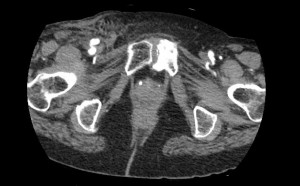

The diagnosis of a pseudoaneurysm is usually made with an ultrasound duplex. There are several signs that a sonographer looks for when insonating with a pseudoaneurysm in mind:

- A mass of blood next to the common femoral artery

- A connection between the mass and the artery (the “stem” of the pseudoaneurysm)

- The power doppler characteristics of blood flow in the stem are to and fro (back and forth). This represents the relationship between the hight pressure artery and the low pressure pseudoaneurysm.

In both cases of pseudoaneurysm and arterio-venous fistula, visualization should be made carefully from the level of the external iliac vessels and down toward the femoral vessels, as not to miss a finding.